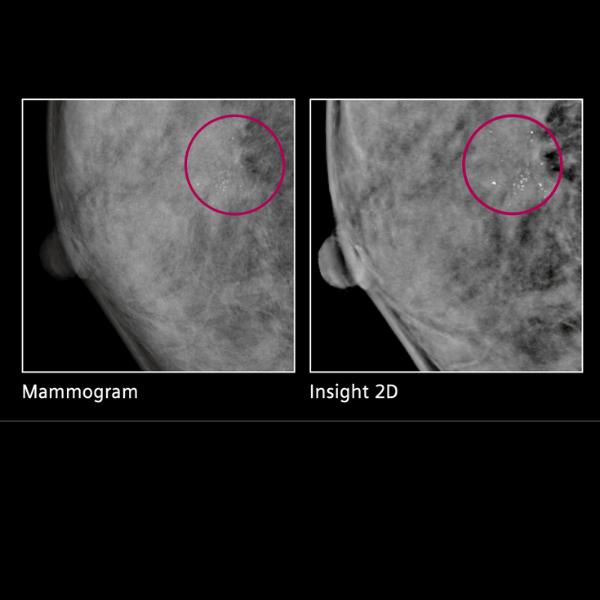

Los equipos Mammomat Inspiration ofrecen un flujo de trabajo simplificado y altamente automatizado, reduciendo pasos operativos y guiando intuitivamente al personal clínico durante toda la biopsia estereotáctica, lo que mejora la eficiencia en el diagnóstico. La configuración automática del modo estereotáctico y la adquisición de imágenes desde una sola estación de trabajo agilizan el proceso y aumentan la confianza diagnóstica.

Además, estos sistemas son compatibles con una amplia gama de agujas (número núcleo, vacío, finas y de localización), ofrecen acceso preciso a lesiones tanto vertical como lateralmente, y permiten tener todas las imágenes previas, posteriores y de muestra en un solo monitor.